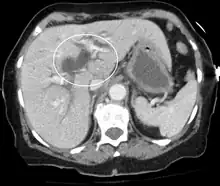

Imaging

Medical imaging such as ultrasound, CT scan, and HIDA scan are useful for detecting bile-duct blockage.[41]